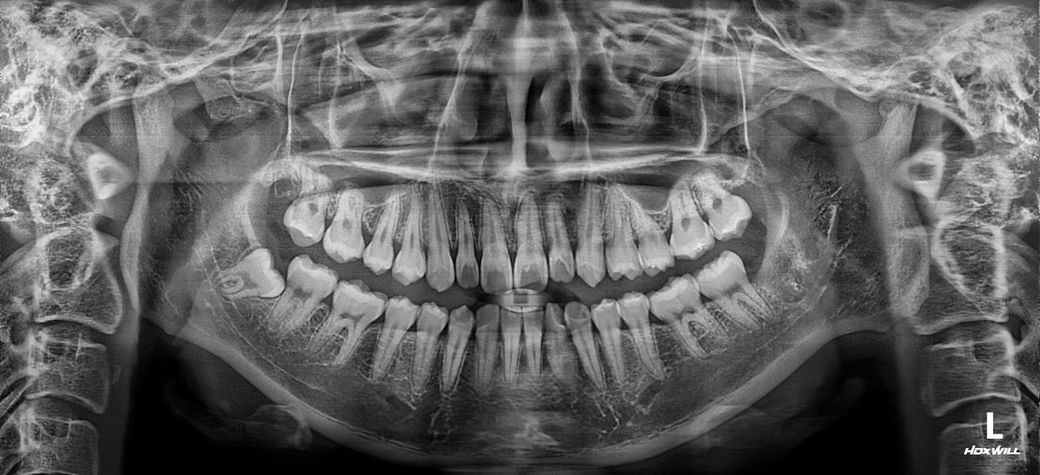

20대 초반이고 잇몸에 통증이 있어서 치과 방문 했어요. 스케일링은 한두달전쯤에 했습니다. 잇몸치료 아래 앞니랑 오른쪽 어금니쪽 해야될거 같다고 하시는데 하는게 맞나요? 잇몸이 더 내려가거나 하진 않나요? 하게된다면 치주과 전문의에게 꼭 해야하나요?

엑스레이 상으로는 크게 잇몸이 안좋거나 그래 보이진 않습니다. 스켈링을 받으시면서 관리 하시면될것같습니다.

잇몸치료는 꼭 치주과 전문의에게 받으실 필요는 없고 사진상으로도 꼭 필요해보이진 않습니다.

사진으로 봤을 경우에는 잇몸의 상태는 매우 좋아보입니다. 또한 큰 치석이 엑스레이상에 보이진 않습니다. 하지만 잇몸 위에 치석이 많이 있는 부분이 있었다면 스케일링을 해서 잇몸 위치적을 제거해도 잇몸 안에 치석에 남아 있는 경우가 있습니다.

이런 경우에는 잇몸 치료가 필요할 수도 있기 때문에 치과에서 진료를 받아보는 것이 좋습니다.

아래 앞니와 오른쪽 어금니 쪽에 잇몸에 염증이 있는 것으로 보이기에 치료를 받는 것을 권합니다.

방치하면 잇몸 염증이 악화되고, 결국 잇몸이 더 내려가거나 치아 지지 조직이 손상될 수 있습니다.